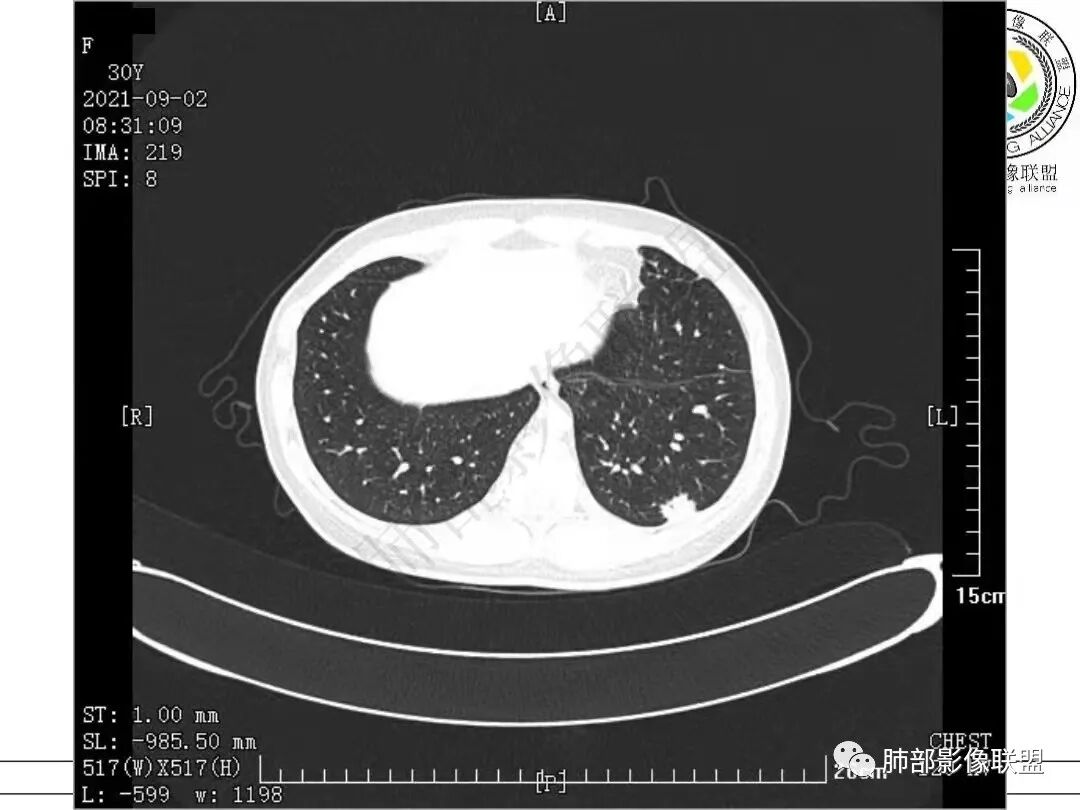

病例二

2.病例二:30岁女性,发现病灶6个月前有咳嗽咳痰及治疗史,肿瘤标志物阴性。左肺下叶胸膜下结节影,整体较膨隆,局部边缘较平直,可见毛刺,同样可见磨玻璃密度区,病灶内可见空泡征,周围可见细小毛刺及多发棘突影,同样外围病灶支气管情况难以判断。邻近肺组织内可见多发微小结节影。病灶张力不高,未见分叶及胸膜牵拉,由于纵隔窗图像太少,不宜判断胸膜下脂肪间隙有无受累,可疑胸膜下有微量积液。

病例二讨论

左肺下叶病灶,边缘分叶,边缘平直,胸膜牵拉不著,像多病灶融合,考虑感染性病变,隐球菌可能

女,39岁,咳嗽半年,左肺下叶结节影,边界清晰,边缘见浅分叶及短毛刺,病灶呈宽基底与胸膜相连,病灶边缘少许晕影,考虑炎性病变。

左肺下叶胸膜下多发结节,互相融合,支气管进入截断,护墙,考虑隐球菌,鉴别浸润性腺癌。

青年女性,左肺下叶外基底段胸膜下结节影,边缘清晰,密度不均,似有多结节融合,支气管进去后截断。考虑炎性肉芽肿病变,隐球菌或慢性机化性炎症